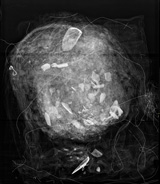

マスク Mask image

ペルーの「false head(人工の頭)」と呼ばれるマスクのX線画像は,この中に貝殻が詰められているという驚くべき事実を明らかにした。貝殻は意図的にマスクの詰め物に使われており,食事を提供する意味があったと考えられるが,他の遺物には,貝殻が詰められたものはなく,その目的は不明。